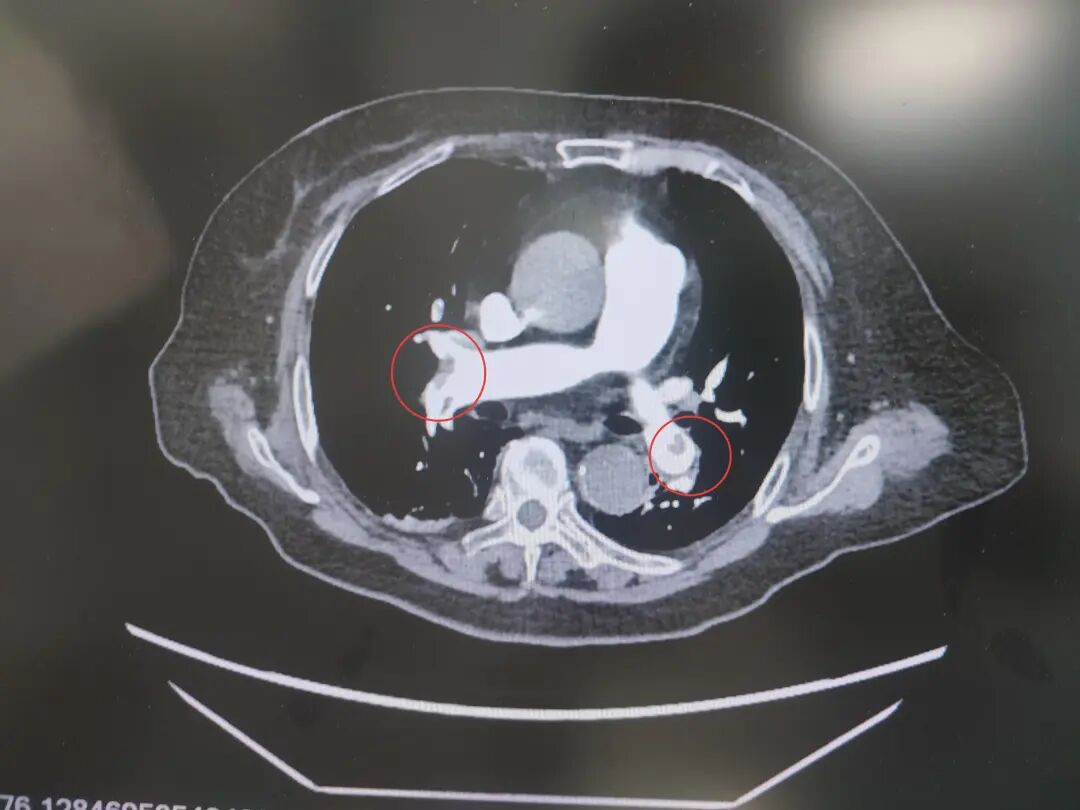

患者高血压病史7年,最高血压达190/100mmHg,2型糖尿病7年,控制不佳。发病前3天,意外摔伤致股骨颈骨折,后出现咳嗽、呼吸困难、胸痛等症状,被紧急送到我院急诊。完善相关检查后,明确诊断为中高危肺栓塞——这是一种足以危及生命的急症,病情进展迅速。

肺占位

为进一步精准救治,呼吸与危重症医学科宋刚主任带领团队对患者进行全面评估,结果令人揪心:肺血栓栓塞(中高危)、I型呼吸衰竭、肺占位性病变、急性冠脉综合征、急性肾功能不全、肝功能不全、脓毒症等多种疾病,且随机血糖高达31.68mmol/L,远超正常范围,生命体征岌岌可危。